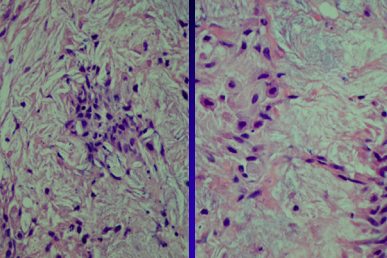

Here is your histopath description. What is your top differential?

“The epidermis is mildly acanthotic. There is diffuse granulomatous inflammation composed of large macrophages containing abundant, foaming cytoplasm. Foamy macrophages are between the collagen bundles as well as in diffuse sheets along the dermis obscuring the normal architecture. Giant cells are seen. There are small lakes of extracellular, amorphous and pale staining lipid deposits”

Xanthoma